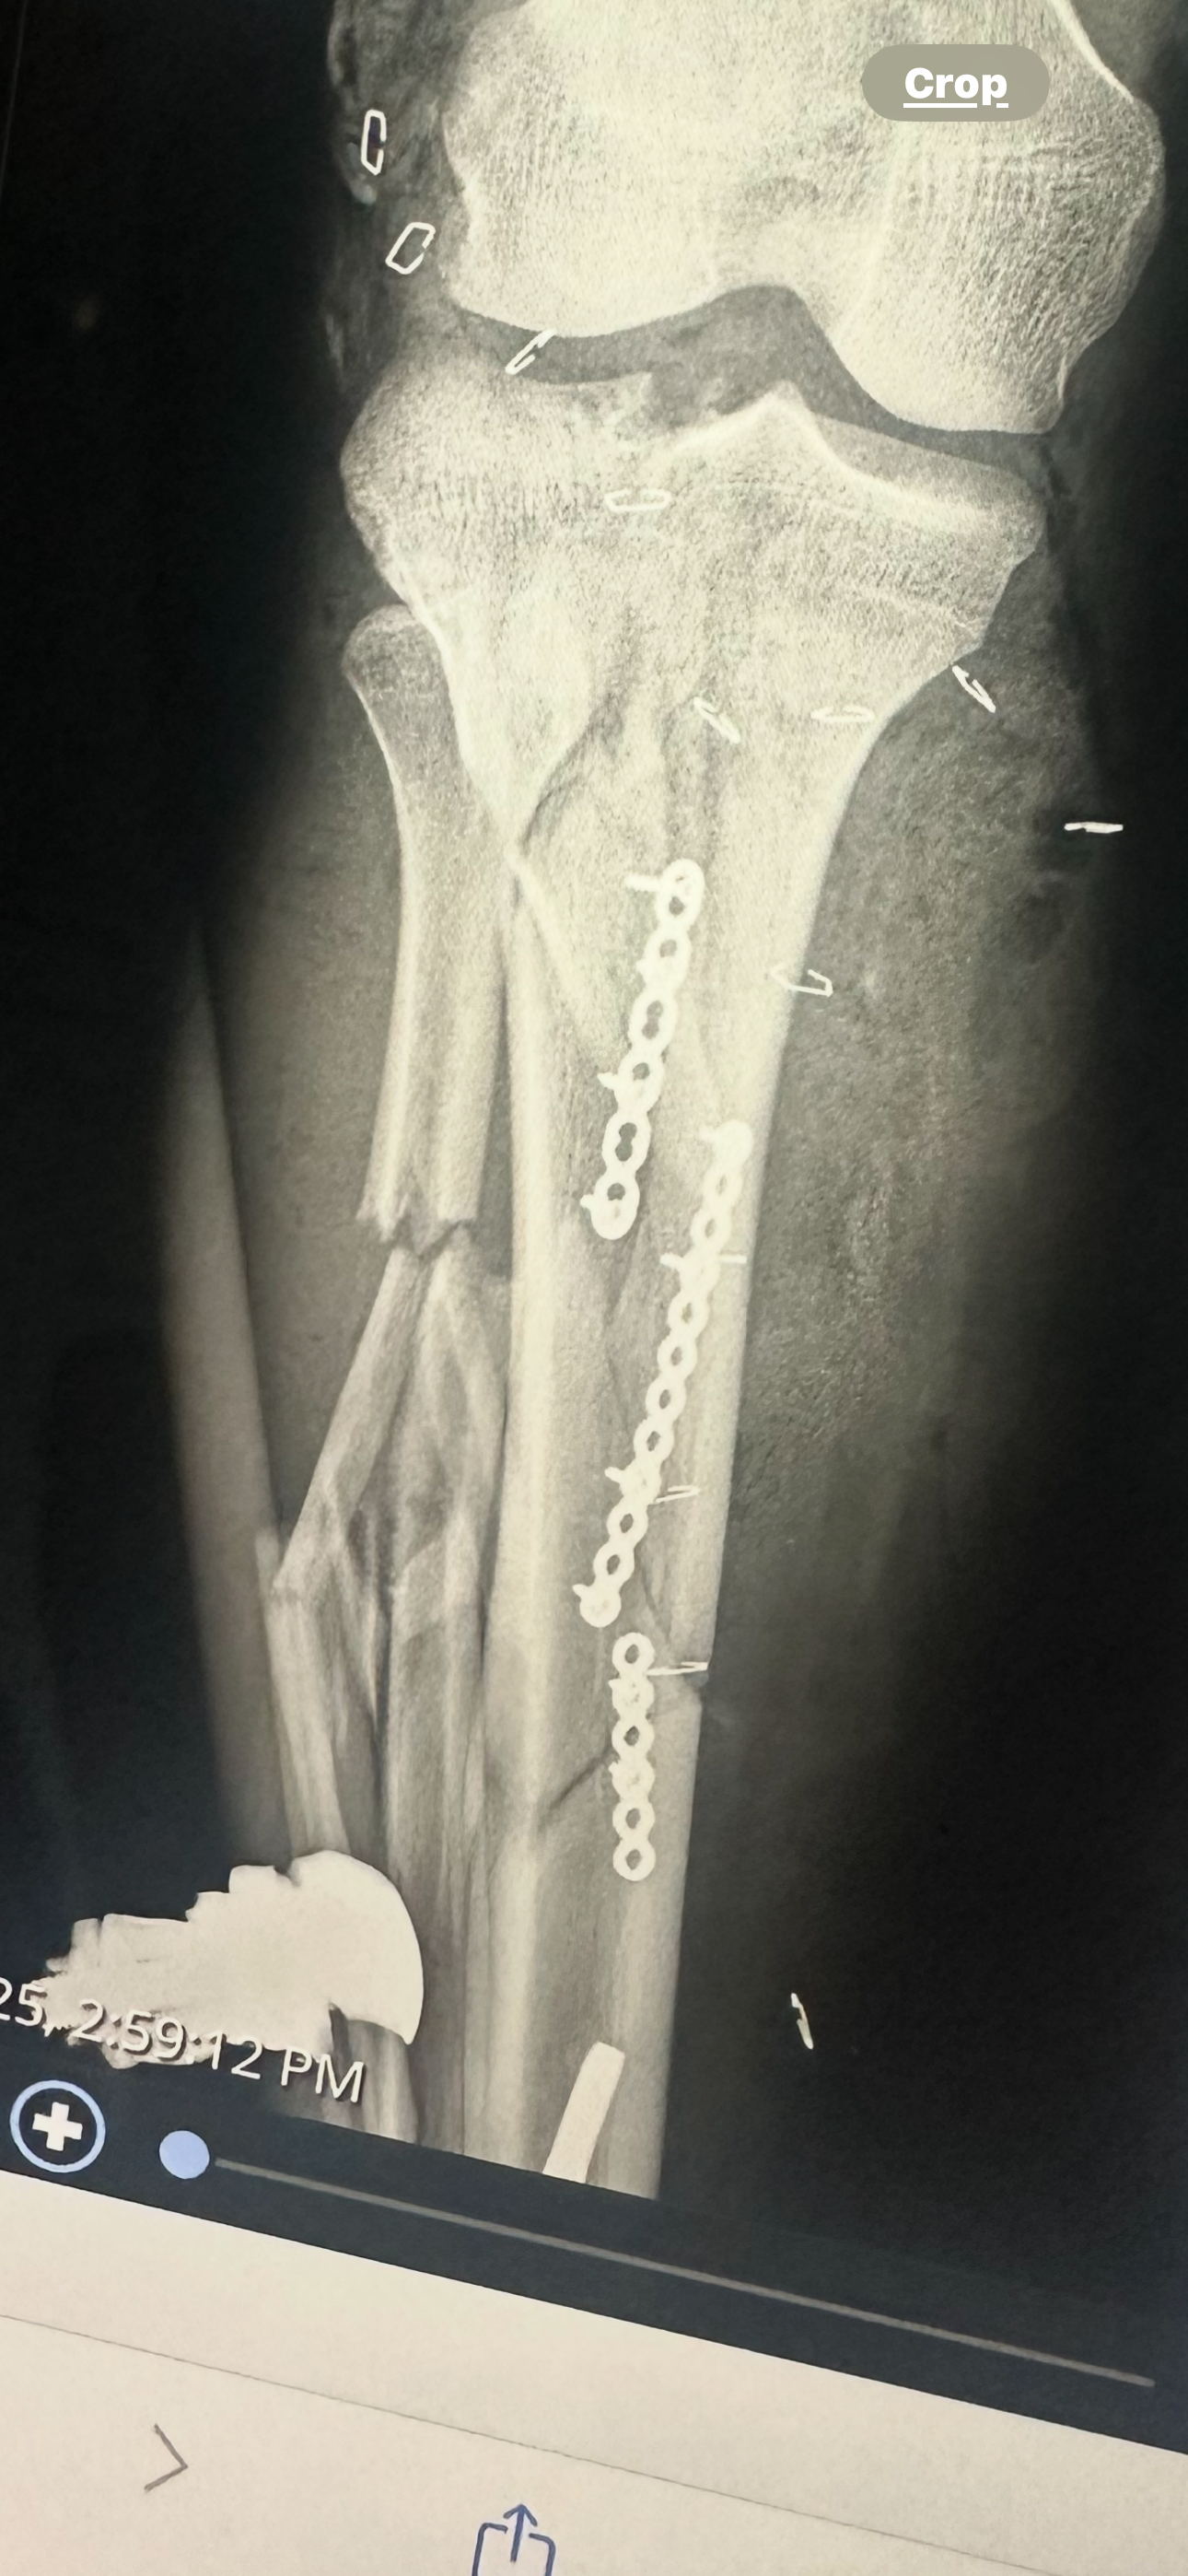

We are trying to help out our friend Tony. He had an accident where he totaled his bike and severely injured his right leg. I’m reaching out to raise some money to save his leg, pay hospital bills, and keep him steady during the healing process where he cannot work.